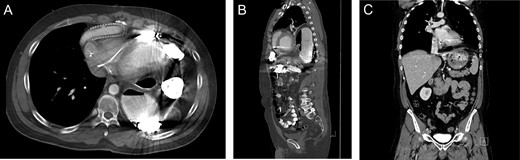

A 43-year-old male with a past medical history significant for non-ischemic cardiomyopathy (NICM) treated with a Heartmate II LVAD and a biventricular implantable cardioverter defibrillator presented to the emergency department with new-onset change in vision, weakness of hands and numbness of upper extremities. The patient was admitted for a TIA evaluation. Due to complaints of daily vomiting a barium swallow was ordered, which demonstrated mesenteroaxial gastric volvulus. A subsequent CT scan demonstrated a diaphragmatic hernia (Fig. 3A and B) and the patient was brought to the operating room for robotic repair of the diaphragmatic hernia.

Imaging from Case #2. (A and B) Preoperative CT scan demonstrating loop of bowel in the thoracic cavity posterior to the heart and LVAD. (C) Postoperative CT scan, coronal view demonstrating repair of the diaphragmatic defect with mesh overlay.

A diaphragmatic hernia was noted immediately adjacent to the LVAD. The herniated intestinal contents were reduced without signs of visceral ischemia. A 20-cm round Parietex mesh was used to bridge the hernia defect, incorporating the LVAD device. The mesh was secured to the diaphragm using running 0-prolene suture. Postoperative course was uneventful and the patient was discharged following therapeutic anticoagulation. Postoperative imaging revealed repaired diaphragmatic defect without evidence of recurrence (Fig. 3C).